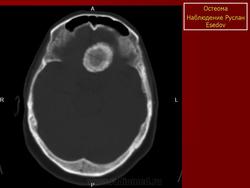

Онкология. Остеома. +

Остеома.

Остеома - это опухолеподобный узел очень плотной кости, при микроскопическом исследовании обнаруживающей все признаки нормальной костной ткани. Излюбленная локализация - кости черепа (у мужчин в 2 раза чаще, чем у женщин) и лицевые кости (в 3 раза чаще у женщин). Некоторые остеомы прорастают в полость черепа и могут сдавливать нервные стволы. Наличие остеомы в одном из параназальных синусов обычно сопровождается симптомами обструкции дыхательных путей. При наличии множественной остеомы или вовлечении в процесс длинных трубчатых костей речь идет большей частью о синдроме Гарднера. Обычно отмечаются опухолеподобные разрастания костной ткани по наружной поверхности той или иной трубчатой кости (так называемая паростальная остеома), которые при рентгенологическом исследовании могут иметь вид неравномерных волнистых утолщений кортикального слоя. Под микроскопом выделяют два типа остеомы. Первый тип, встречающийся наиболее часто, состоит из очень плотной компактной кости, другой - представляет собой пластинчатую кость, в ячейках которой располагается фиброзно-жировая ткань или же кроветворный костный мозг, его называют губчатой, трабекулярной или смешанной остеомой. При дифференциальной диагностике, помимо реактивного разрастания костной ткани, остеому следует отличать от оссифицированной фиброзной дисплазии и солидной одонтомы. В длинных трубчатых костях остеому необходимо дифференцировать от организованной периостальной мозоли и остеохондромы с эбурнеацией хрящевых капсул. Остеому трудно отличить от реактивных разрастаний костной ткани после инфекционного поражения, травмы, а также старых остеохондром с атрофированными хрящевыми краями.